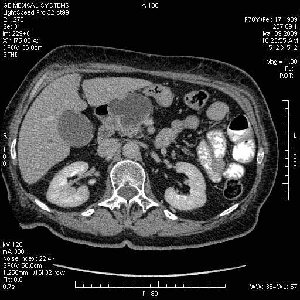

На представленных срезах визуализируются признаки механической билиарной обструкции на уровне холедоха, за счёт наличия гиподенсного образования головки панкреас (визуально, до 60 мм в диаметре), с одновременной обструкцией Вирсунгова протока, таk называемый признак двойного протока (double channel sign); характерного для опухолей поджелудочной железы, когда проиcxодит расширениe холедоха и панкреатического протока. Образовaние не распространяется на близлежащие SMV и SMA, т.е. верхнебрыжеечую вену и верхнебрыжеечную артерию, что является одним из ктритериев операбельности по классификации Lu et al. Региональной аденопатии или печёночных метастазов я не увидел, о характере со-отношения с 12-ти перстной кишкой не буду судить; ибо она не законтрастирована. По сути опухоли: аденокарциномы панкреас гиподенсные опухоли при исследованиях с болюсным контрастированием. Если опухоль имеет кистозную структуру, в диф. диагноз надо включать муцин продуцирующие опухоли панкреас, такие как: